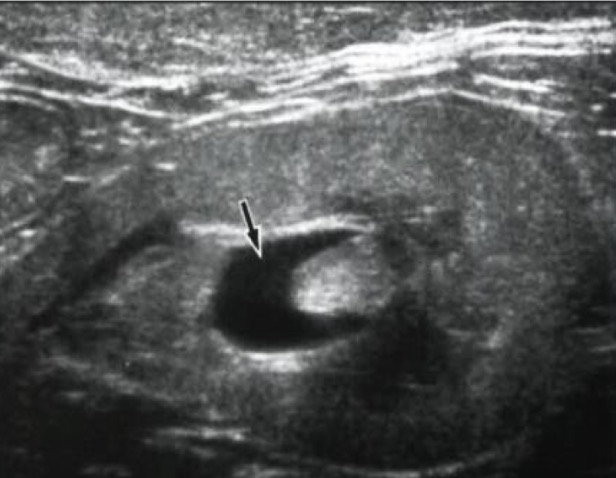

Hydronephrosis

What is this arrow pointing to?